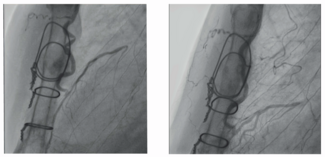

Byeng-Ju Son, MD; Jong-Seon Park, MD, PhD; Ung Kim, MD, PhD; Kang-Un Choi, MD, PhD; Jong-Il Park, MD

An 82-year-old woman was admitted for non-ST elevation myocardial infarction. At the coronary angiography, diffuse significant stenosis of the right coronary artery was observed.